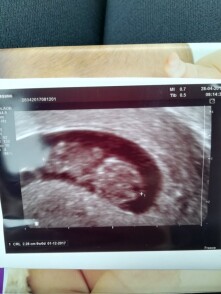

dobru den mozem sa opytat nieco ohladne otehotnenia?mam iba jednu sonografiu od mojej ex priatelky.tvrdi ze je tehotna somnou i ked mi niejake veci na nej nesedia.Myslite zeby ste sa vedeli pozriet na tu sonografiu a mozno mi napisat odkedy dokedy mala ovulaciu?viem ze to bude tazke ale chcem len taky nezavisly nazor.Boli sme spolu od 7.3 do 11.3(maly sme sex) na sonografii dole v pravom rohu su datumy: 01.12.2017 9w/0pripajam fotku dakujem za odpoved s pozdravom